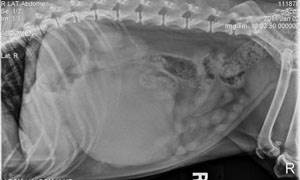

Визуальная диагностика состоит из рентгенограммы брюшной полости, грудной клетки, УЗИ брюшной полости. С помощью данных методов врач может обнаружить опухоль, установить ее точную локализацию, оценить размер. Также выявляются отдаленные метастазы и сопутствующие опухолевые процессы.